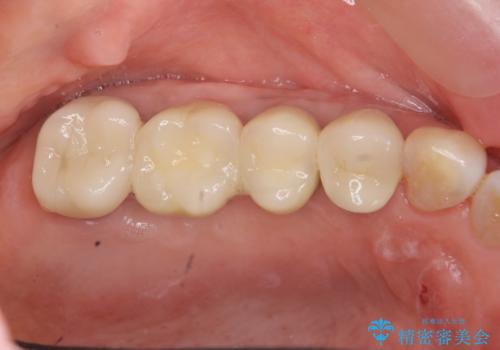

インプラント治療が終了し、しっかりと咬合機能が回復しまた食事が楽しめるようになりました。